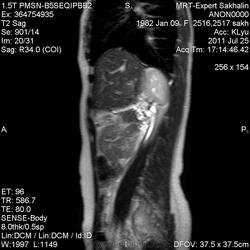

Девушка, 28 лет.В 14 лет перенесла операцию -резекция хвоста поджелудочной железы (!) по поводу опухоли.В 2000 г-выявлены множественные образования печени. В 2006 году резекция 4-ого сегмента печени.

Но заинтересовал он меня по другому поводу-обратите внимание на печень и почки.

Бросается в глаза увеличенная правая почка.Левую нашла только на постконтрасте-резко гипоплазирована.Печень занимает всю эпигастральную область, увеличена.Данных за рецидив опухоли ( по гистологии-примитивная нейроэктодермальная опухоль) не выявлено.

У пациентки удвоение правой почки.Гипоплазия левой-примерно 2.0х2.0х2.5 см, но архитектоника ее( насколько могла разглядеть) не нарушена, распологается где-то на уровне 3-4 позвонков.

Надпочечники тоже достоверно не визуализируются-слабо развита параадреналовая клетчатка.

Печень увеличена-думаю, что викарная гипертрофия после резекции.Желчный пузырь также отсутствует после холецистэктомии.Отсутствует хвост и часть тела поджелудочной железы.

Под печенью-оттесненный желудок ( светлый неоднородный из-за наличия жидкого содержимого).

Поперечно-ободочная темная из-за наличия газа, расположена ниже.